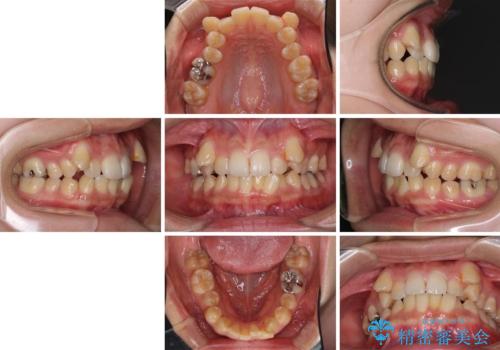

- 下の前歯のデコボコを気にして来院された患者様です。

来院当初、上顎の八重歯は気にしていらっしゃらなかったのですが、矯正治療をするのであれば、しっかりと治した方が良いと説明し、全顎矯正を行うこととしました。

八重歯の移動量が多く、インビザライン単体での治療は困難と判断し、補助装置により八重歯移動後にインビザラインを用いることとしました。